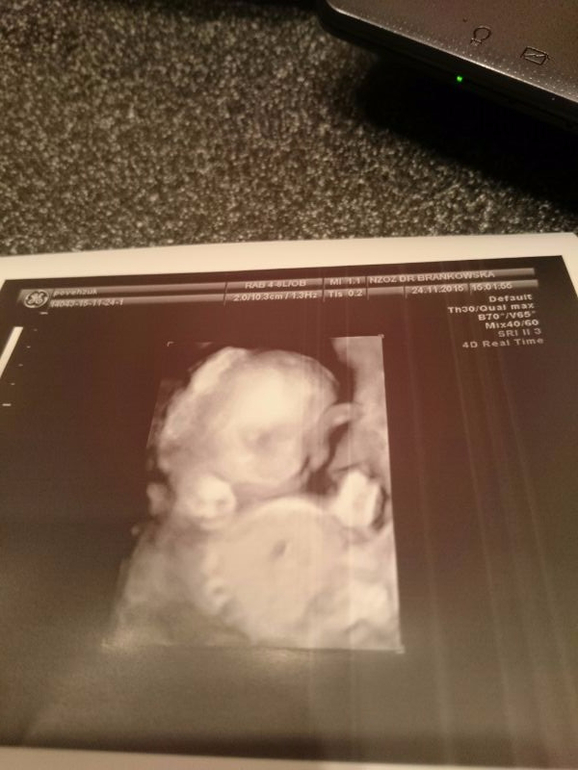

Наше УЗИ 20+6 ))

Результаты: УЗИ, КТГ, доплера, скринингаЮхуууу нам подтвердили нашу девочку)))

Итак весит наша доченька около 450 грамм.Сердечко 152 удара .Как крутилась и вертелась это просто капец

Все измерения в норме ттт.Переписывать даные не буду так как на польском языке а переводить не охота.

Понятно что качество желает лучшего.Сделали нам ровно 30 фотографий))))Много но есть из чего выбрать))))

Спасибо)))) Мы на обычное УЗИ ходим, но нам каждый раз делают измерения в 2D(или как там обычное УЗИ называется) а потом фото в 3D.